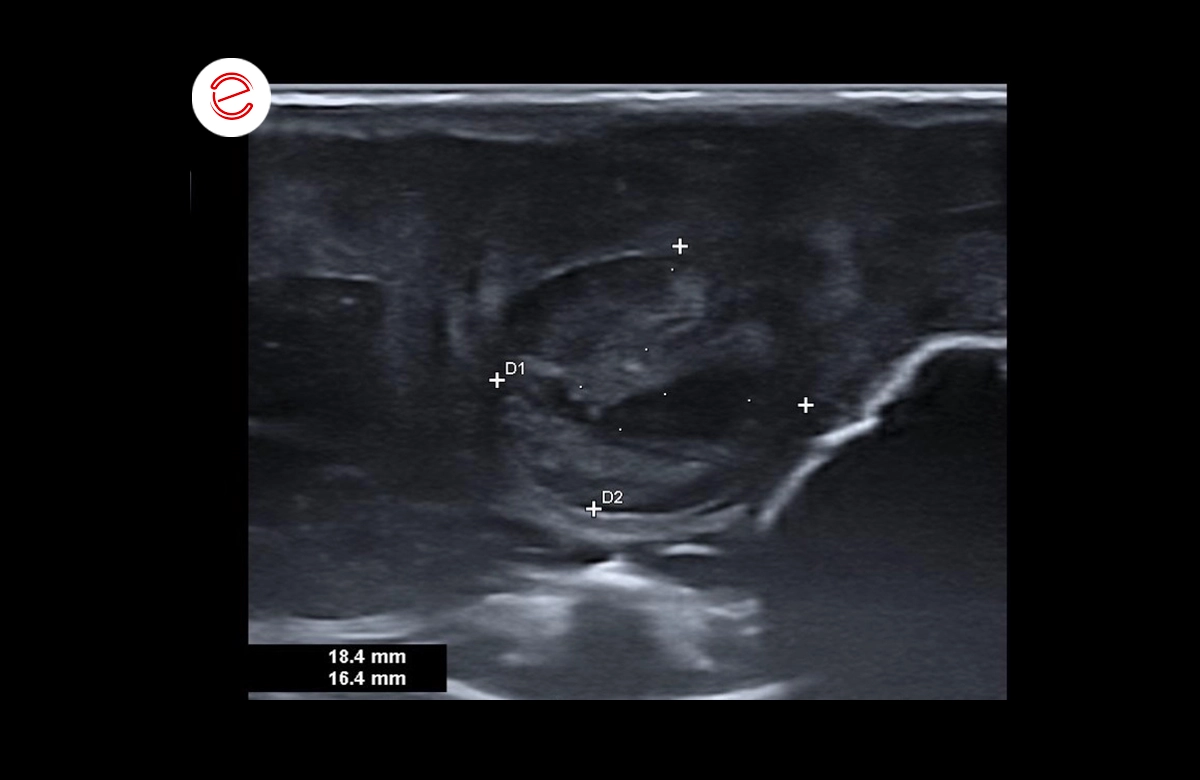

The liver is enlarged in size with rounded margins, parenchyma deformed by several oval-shaped masses, with regular contours and variable degrees of heterogeneous echostructure.

The largest mass measures approximately 3 cm in long-axis diameter.

Distended gallbladder, thickened and irregular wall, showing mobile echogenic sediment in the slopes and hyperechogenic punctures with some posterior acoustic shadowing.

Images were acquired using the MyLab™Omega VET system.

The characteristics of the liver masses and the animal's clinical picture were suggestive of neoplasia (primary or secondary) or severe chronic nodular hepatitis. An echo-guided aspiration puncture was performed for subsequent cytological analysis. (d.d: hematoma, abscess).